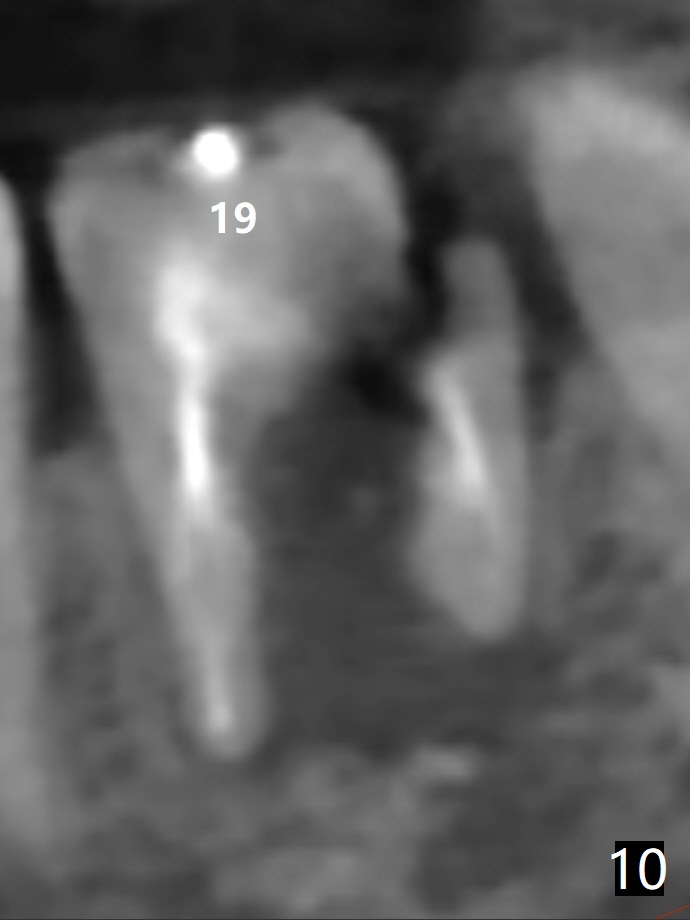

A 61-year-old woman with history of bruxism returns to clinic with chief complaint "I cannot chew bottom right. Top left has had pain and swelling before". Exam shows loose FPD at #31 (Fig.1) and necrosis of #14 (Fig.2). When the FPD is sectioned, the tooth #31 is found to have subgingival caries, filled with IRM (Fig.3). CT shows large PARL around MB and P roots of the tooth #14 (Fig.4), the fractured distal root of the tooth #19 with the low buccal plate (Fig.5) and a 5x10 mm implant being able to be placed at #30 (Fig.6). The crestal cortex (Fig.7 arrowheads) is thin in the edentulous area for several decades. The bone density is low (Fig.8, underprep). To place an implant over the pointed ridge, it should be trimmed prior to osteotomy (Fig.9). The bone loss associated with the fractured distal root is severe at #19 (Fig.10). After removal of the mesial root (Fig.11: 1), perform distal socket shield (2).